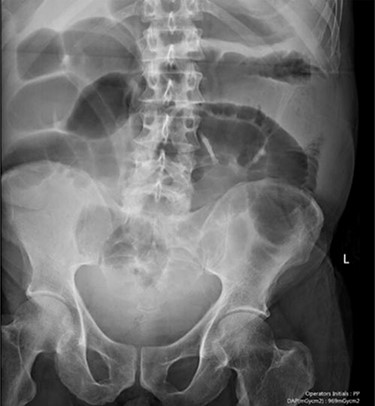

Blood tests on admission were unremarkable, with normal electrolytes levels and lactate. A plain abdominal film showed a typical appearance of caecal volvulus, with an inverted ‘comma sign’ (Fig. 4). A CT scan of the abdomen and pelvis with intravenous contrast was reported as sigmoid volvulus with the involved loops sitting predominantly in the right upper quadrant immediately inferior to the liver (Fig. 5).

Case two: a coronal slice of a CT scan of the abdomen and pelvis with intravenous contrast showing dilated large bowel loops; the radiology report suggested sigmoid volvulus with a centrally lying caecum.